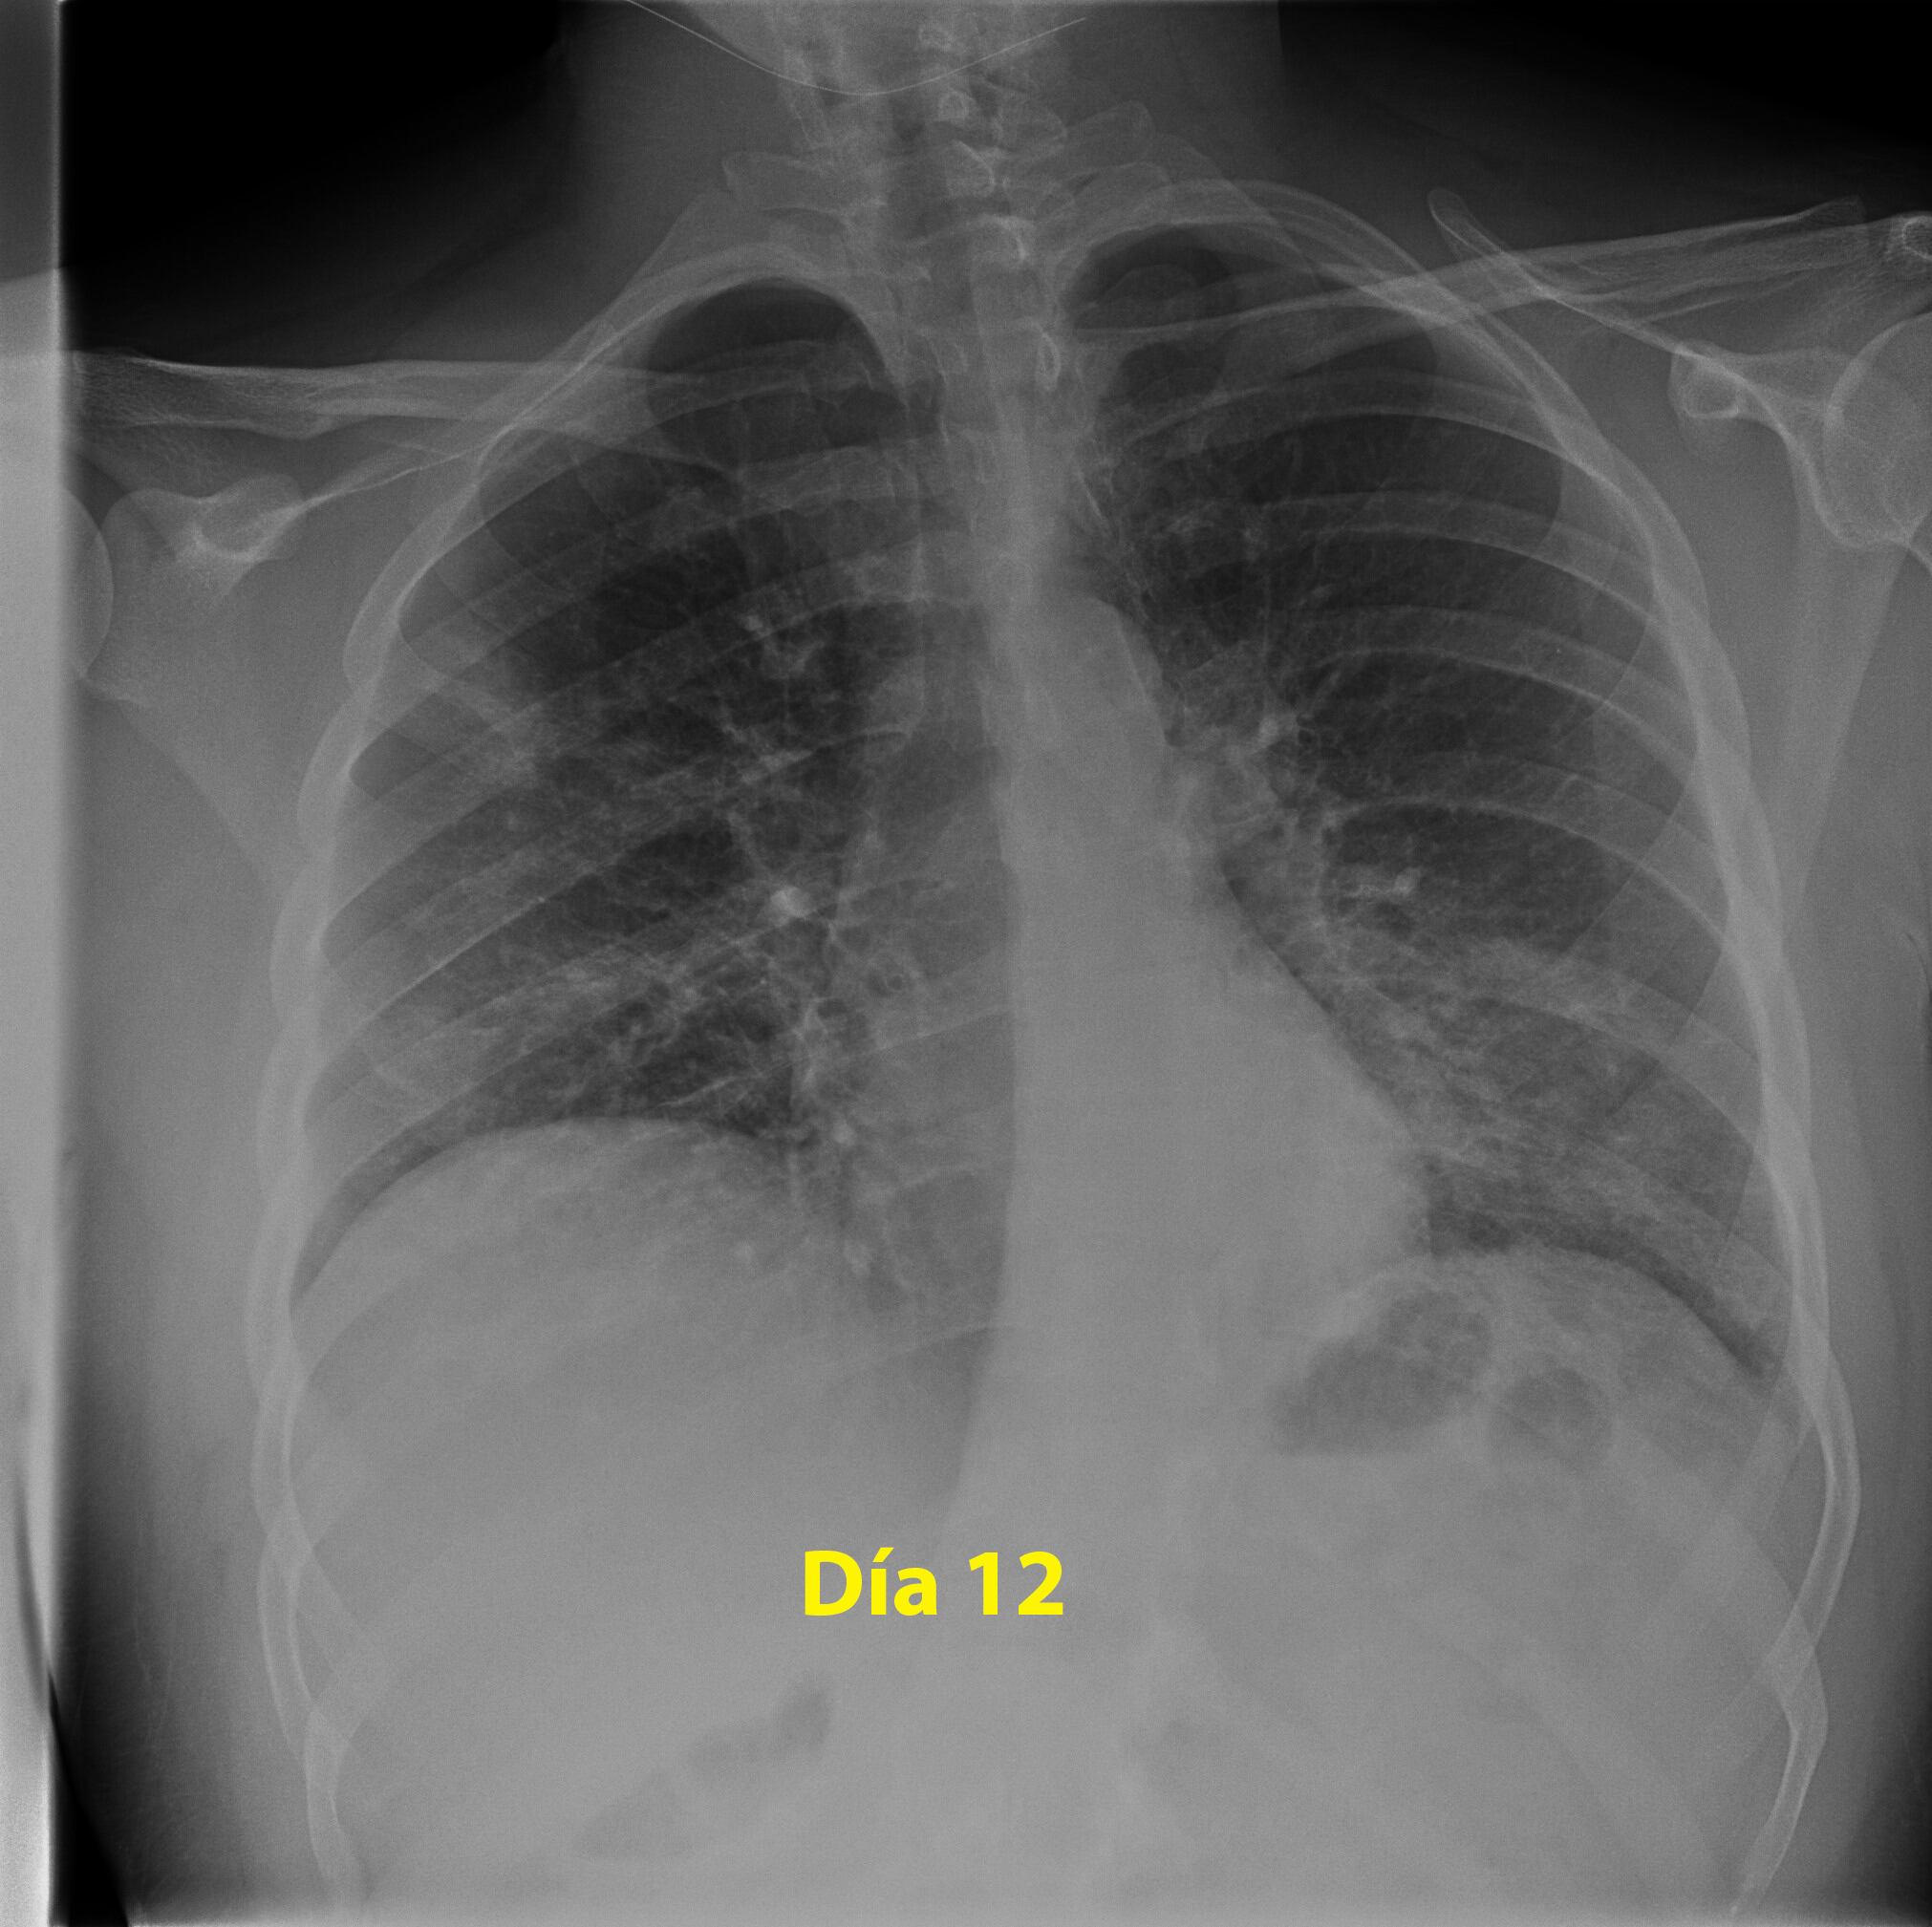

Si bien se puede pensar que Joseph no se encontraba en el grupo de riesgo debido a su edad; el padecer fibrosis quística elevaba la peligrosidad del Covid-19, teniendo altas probabilidades de afectarlo de manera permanente e incluso quitarle la vida.

Esto debido a que su padecimiento ataca de manera continua sus glándulas exocrinas, dando como resultado un funcionamiento deficiente en las mismas. Esto provoca problemas en el páncreas y los pulmones.

El coronavirus, al ser una enfermedad que afecta principalmente las vías respiratorias, tenía altas probabilidades de encontrar debilitado el organismo y defensas de Joseph, que constantemente se ve asediado por la fibrosis.